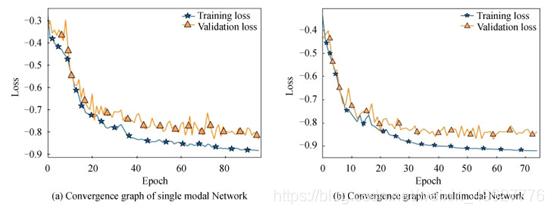

为验证本文采用的多模态融合方法的有效性,将单模态Flair与多模态融合的MRI影像进行实验对比,将预先分配好的228例样本作为训练样本,57例样本作为测试样本,脑肿瘤检测网络训练集及测试集的网络收敛图如图 7.

图 7 不同模态脑肿瘤检测网络收敛示意图

从图 7可知,单模态脑肿瘤检测网络训练集和测试集的损失值分别为-0.882 6和-0.831,多模态脑肿瘤检测网络的损失值可达到-0.911 5和-0.857 7.与单模态网络相比,多模态网络的损失值更小,训练损失值和测试损失值分别提升了0.028 9和0.026 7,表明多模态脑肿瘤检测网络的性能更佳,但从损失函数的收敛曲线来看,多模态脑肿瘤检测网络存在着过拟合的问题.

图 8为测试集57例样本的评价指标Dice分布图,对比图 8(a)和(b)可知,单模态网络中有4例样本远离集群点,而多模态仅有2例样本远离集群点.

图 8 脑肿瘤测试集Dice分布

表 1为不同模态脑肿瘤检测网络训练集57例样本的三种评价指标量化分析对比.可知,多模态脑肿瘤检测网络的三种评价指标Dice、SN和SE分别提升了4.79%、0.15%和0.06%,从测试集的量化结果表明多模态的脑肿瘤检测方法更佳.

表 1 不同模态脑肿瘤检测三种评价指标对比